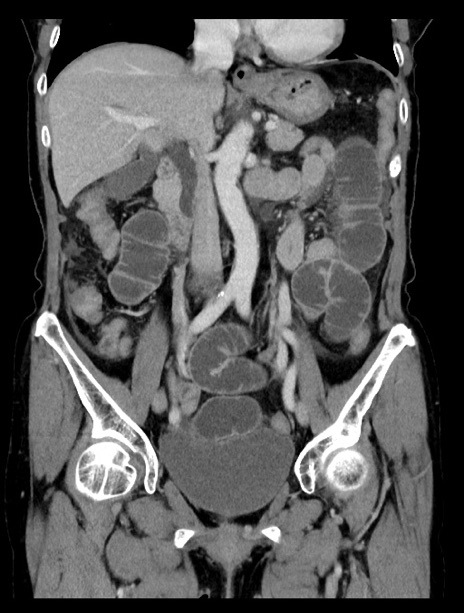

症例23(冠状断像)

【症例】70歳代女性

【主訴】下腹部痛・嘔吐

【現病歴】2日前より腹痛あり。昨日嘔吐あり。症状改善しないため来院。

【既往歴】胃GISTに対して胃部分切除後。

【身体所見】BT 37.1℃、BP 128/77mmHg、腹部:平坦・軟、下腹部に圧痛あり。

【データ】WBC 10200、CRP 0.31